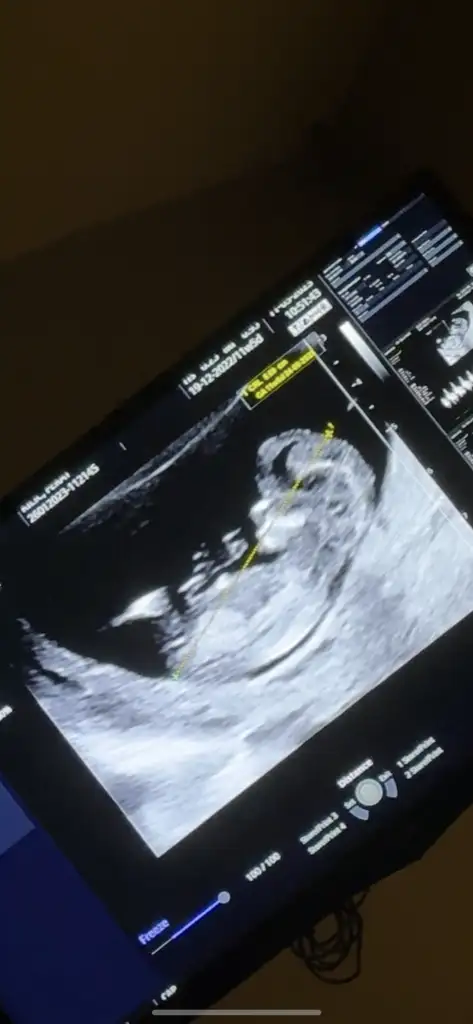

Benimkinide yorumlayabilr misinizzErkek bence

Merhaba anladığınız kadarıyla bana da yorum yaparsanız çok sevinirimcanım bacak arasında net 3 çizgi var cinsiyeti belli kızların 3 çizgisi net olduğunda cinsiyeti de nettir ama 3 cizgi belirmemisse o zamsn söylemez doktorlar erkekler 10 haftadan itibaren belli ediyor kendisini.. birde benim bebeğimde kız bebeğin duruşu yapısı benim bebeğimle aynı ben kiz olduğundan emin oldum ama hakkinda hayirlisi olsun

Sirti donuk sanirim, yan durunca alt kisimdan biraz anlasiliyor ama boyle anlayamadim. Cok da bilemiyorum acikcasi normalde de, sadece tahmin ediyorum gorunce:)Benimkinide yorumlayabilr misinizz

net anlayamadim ama erkek gibi geldi bana hakkinda hayirlisiMerhaba anladığınız kadarıyla bana da yorum yaparsanız çok sevinirim![]()